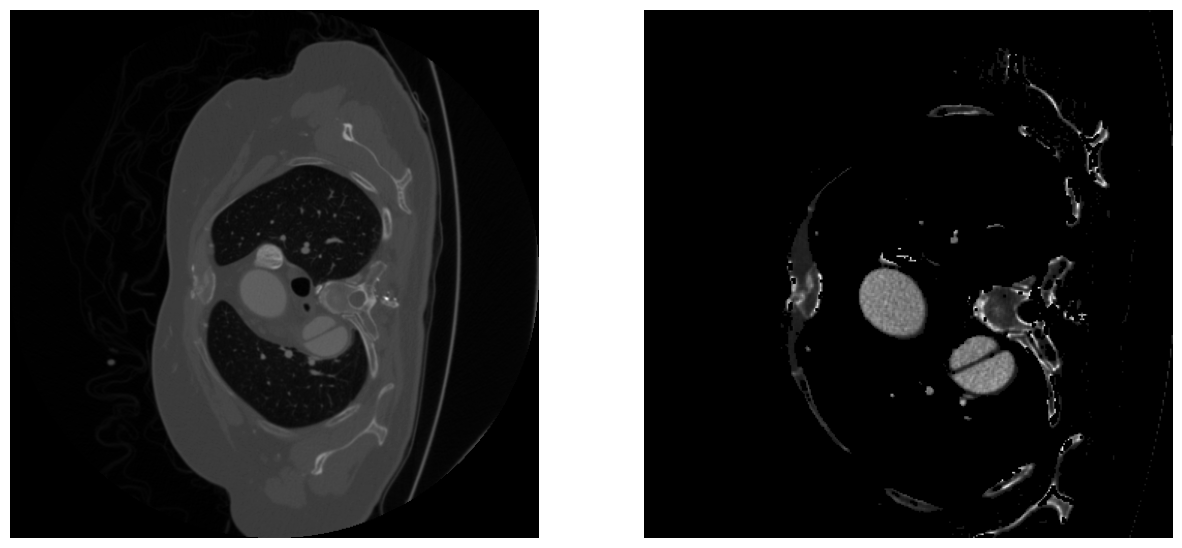

There was also an intensity restriction on the Hounsfield scale, the application of standardization, exponential functions and final MinMax normalization. This helps to highlight important structures in the image and facilitate the segmentation process. An example of image processing code is shown in Listing [lst:preprocess]. An example of the resulting image can be seen in Fig 1.

Figure 1: An example of data preprocessing, before and after.